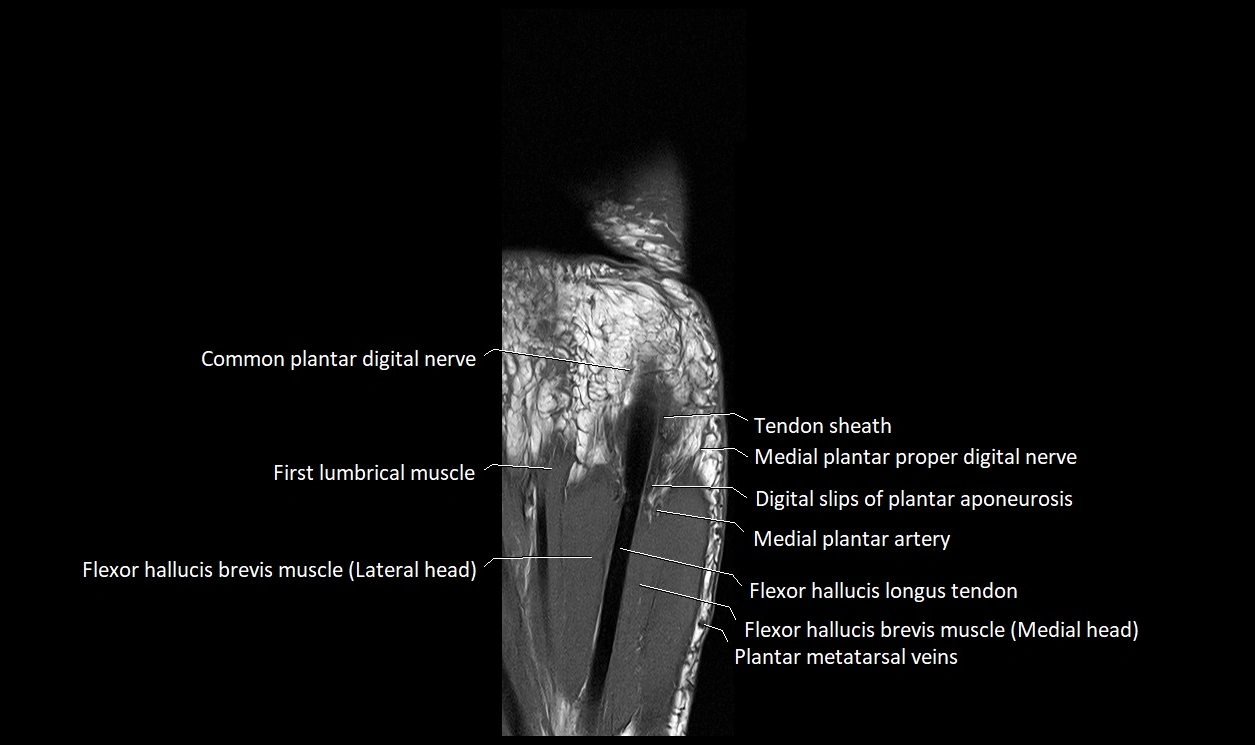

MRI image

image